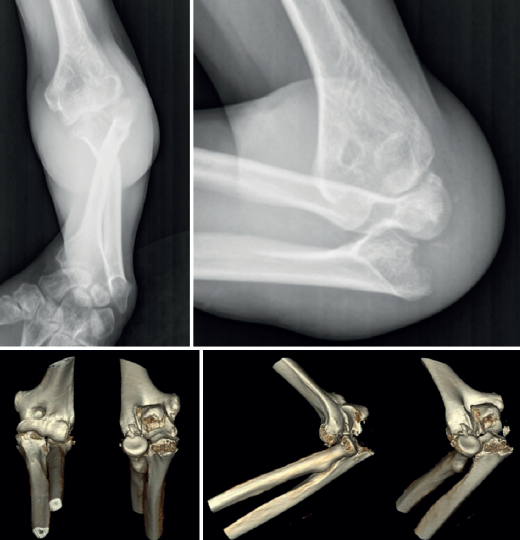

A pesar de que no existe un consenso en relación con la clasificación de las fracturas-luxaciones del codo y ateniéndonos al concepto fractura-luxación transolecraneana, en estas lesiones debe existir una fractura intraarticular del olécranon, con solución de continuidad en la cortical posterior del cúbito, en la que se ve comprometida la estabilidad humerocubital. Si no existe una luxación de la articulación radiocubital proximal, el término adecuado es “fractura-luxación transolecraneana” y, si se asocia una luxación de la articulación radiocubital proximal, “fractura-luxación variante de Monteggia” (Figura 1). Los estudios radiológicos no siempre permiten diferenciar claramente los patrones de fractura por lo que la tomografía axial computarizada (TAC) y especialmente las reconstrucciones tridimensionales son imprescindibles para su diagnóstico.

El desplazamiento del cúbito y del radio con respecto al húmero puede ser anterior o posterior tanto en la fractura-luxación transolecraneana como en la fractura-luxación variante de Monteggia (Figuras 2, 3 y 4). En los adultos, las fracturas-luxaciones transolecraneanas anteriores son menos frecuentes que las posteriores y se diferencian más fácilmente de las fracturas-luxaciones variante de Monteggia de tipo I que las fracturas-luxaciones transolecraneanas posteriores, que frecuentemente se confunden con fracturas-luxaciones variante de Monteggia de tipo II. En ambas lesiones existe una fractura intraarticular del olécranon, pueden asociar una fractura y/o luxación de la cabeza del radio y una fractura de la coronoides y, en las fracturas-luxaciones variante de Monteggia de tipo II, puede asociarse una lesión del ligamento colateral lateral(1,2,13,14,15).